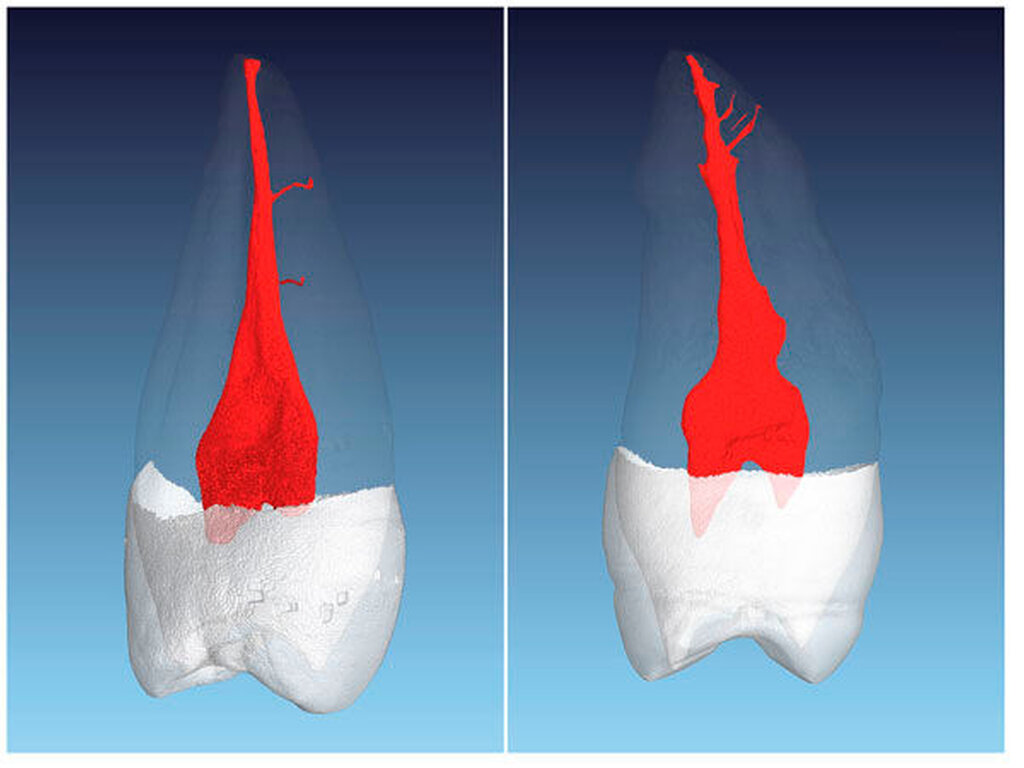

Beim ersten Prämolaren sind fast immer zwei vollständig getrennte Kanalsysteme aufzufinden. Von koronal nach apikal sind die Kanäle meist rund im Querschnitt – nach eigenen Beobachtungen bei hunderten von eingescannten Zähnen sind die Kanalquerschnitte des ersten oberen Prämolaren mit zwei Kanälen im Vergleich zu allen anderen Kanälen im menschlichen Gebiss am ehesten als rund zu bezeichnen – und werden sehr schmal im apikalen Bereich mit zum Teil erheblichen Krümmungen (Abbildung 2).